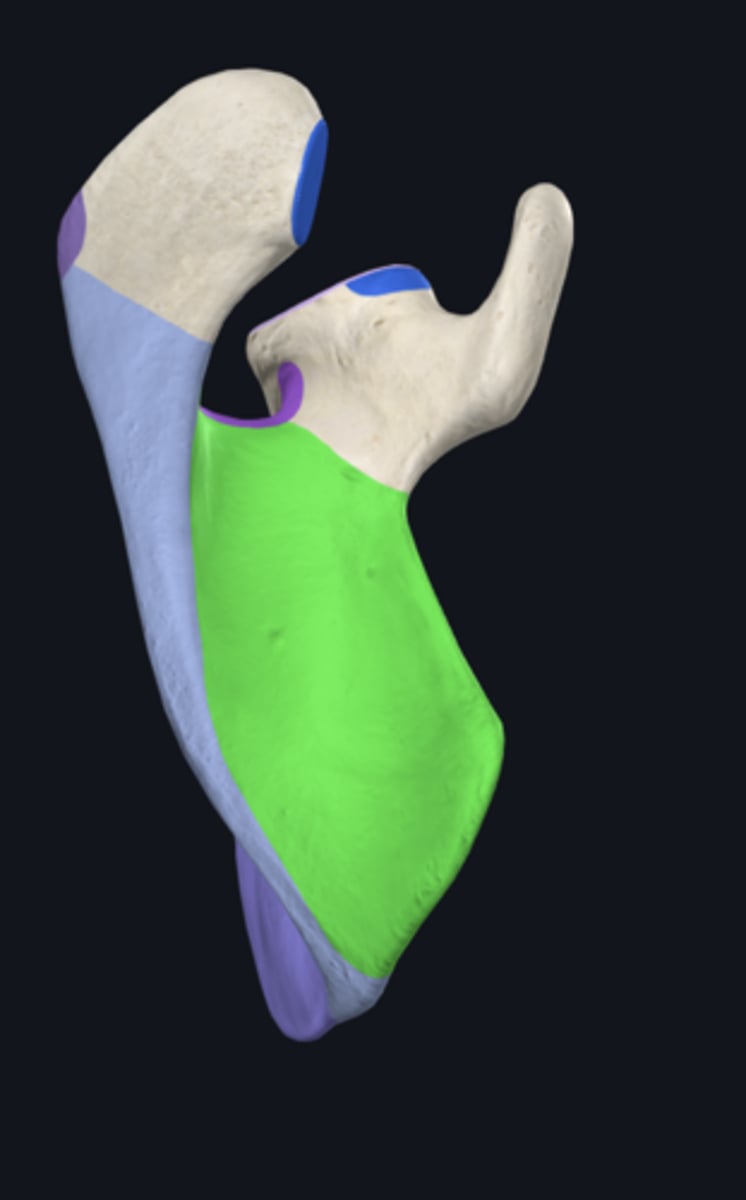

Superior angle of scapula

lateral border of scapula

medial border of scapula

inferior angle of scapula

lateral angle of scapula

scapular notch

superior border of scapula

acromial angle

clavicular facet

spine of scapula